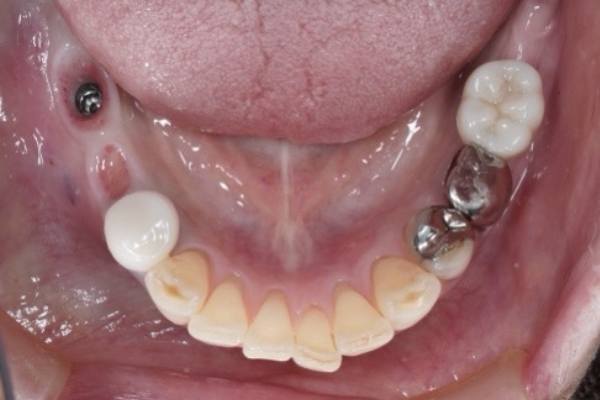

治療後(After)

上部構造装着前

上部構造装着後

インプラントにより奥歯の支持が回復することで、全体の噛み合わせが安定し、他の歯への負担軽減にもつながります。

上顎が入れ歯で下顎は入れ歯にしたくないとのことでインプラント治療を行うこととなりました。ヒビが入っており違和感があった歯がインプラントになりなんでも噛めるようになったと喜んでおられました。今後も長期安定を目指し、定期的なメンテナンスを行っていきます。

| 治療内容 | CTによる精密診断を行い、骨量・骨質・解剖学的リスクを詳細に評価した上で、インプラント治療計画を立案しました。 本症例では、右下6番にインプラントを埋入し、そのインプラントを支点として前方の歯を補うカンチレバー補綴を採用しています。 カンチレバー補綴とは、1本のインプラントで複数歯を支える治療方法であり、 すべての症例に適応できるわけではなく、骨の状態・咬合力・噛み合わせのバランスを総合的に評価した上で慎重に判断する必要があります。 本ケースでは、以下の内容を満たしていたため、安全性を確保したうえで適応可能と判断しました。 ●十分な初期固定が得られる骨条件 ●過度な咬合負担がかからない設計 ●カンチレバー長を考慮した補綴設計 また、インプラント本数を増やすことも選択肢として考えられましたが、 外科的侵襲や患者様の負担を考慮し、最小限の本数で最大限の機能回復を目指す治療戦略を選択しています。 その結果、手術侵襲を抑えながらも奥歯の咀嚼機能を十分に回復し、審美性・機能性ともにバランスの取れた結果が得られました。 |